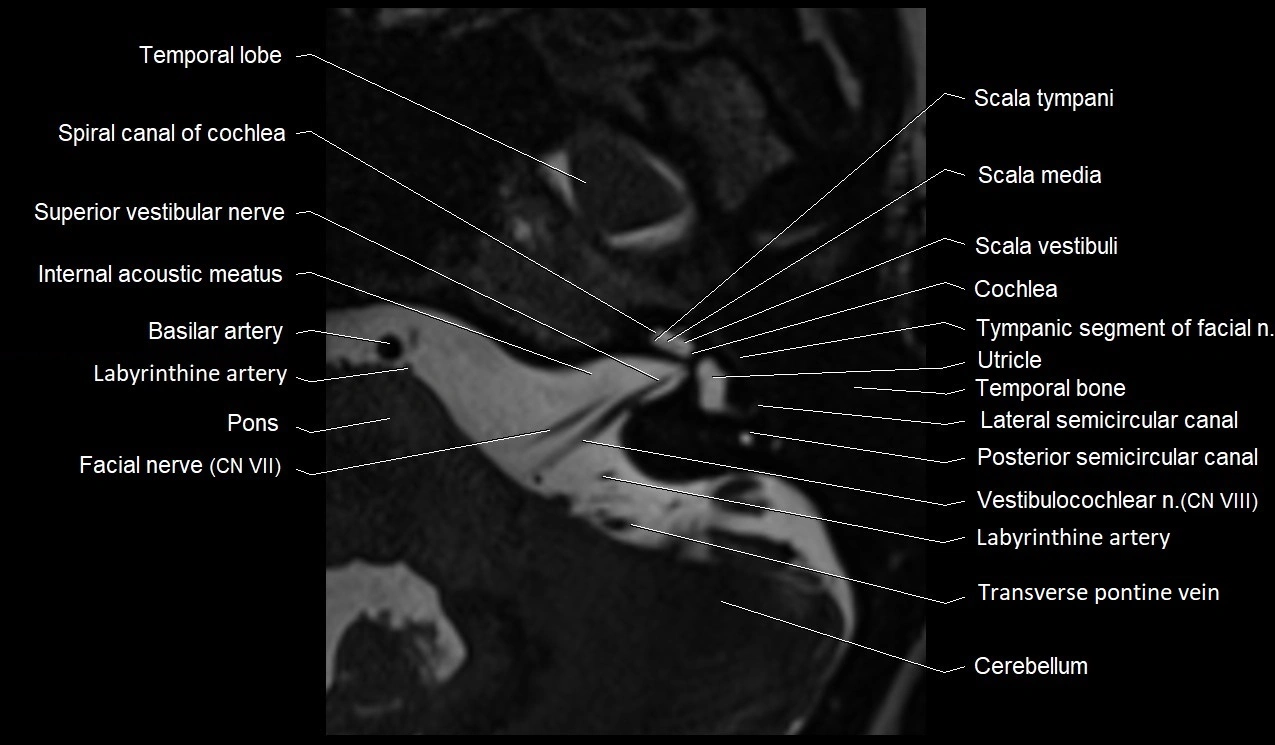

MRI images

image